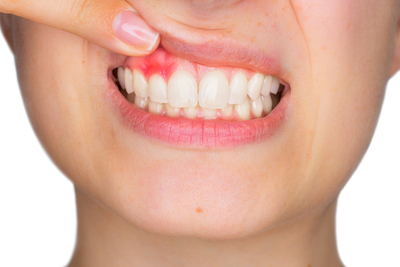

Признаки хронической формы:

Фото 2. Хроническая форма заболевания проявляется застойным переполнением кровью сосудов и отёчностью слизистой дёсен, кровоточивостью и деформацией десны.

- опухшее состояние десны;

- болевые ощущения во время приёма пищи;

- болезненность во время чистки зубов;

- переполнение крови в десне;

- отслаивание дёсенных сосочков от зубов.

Выявить хроническую форму гингивита сможет только врач.